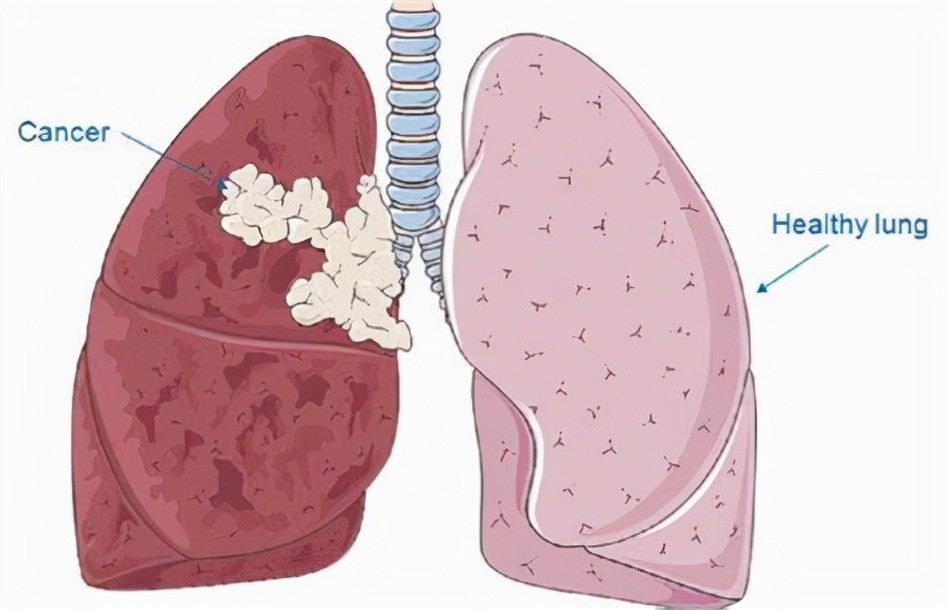

一、什么是肺癌?

在讨论早期症状之前,我们先了解一下肺癌。

肺癌就是肺部的癌症,可是肺癌有多可怕呢,很多人又不甚了解。